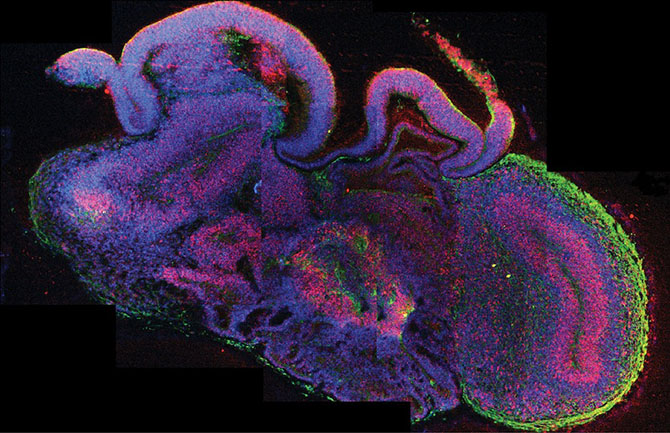

Исследователи из Австрии сделали большой шаг в области исследований мозга — они в буквальном смысле вырастив мозг. Радует то, что этот мозг не плавает в банке, скорее это «мозговые органоиды» всего четырёх мм в диаметре, выращенные из стволовых клеток человека в чашке Петри.

Этот так называемый мини-мозг представляет собой первый случай, когда учёные смогли создать что-то близкое к мозговой ткани в лабораторных условиях. Безусловно, до разумной сущности ещё далеко, но благодаря мини-мозгу удалось узнать, как развивается редкое заболевание под названием микроцефалия. Кроме того, подобные образцы можно использовать для диагностики и лечения других заболеваний вроде аутизма и шизофрении.